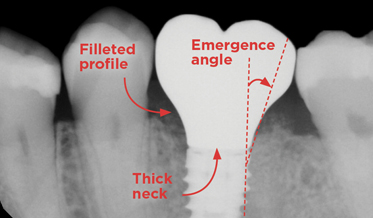

Using Three Familiar Radiographic Shapes to Improve Dental Implant Longevity